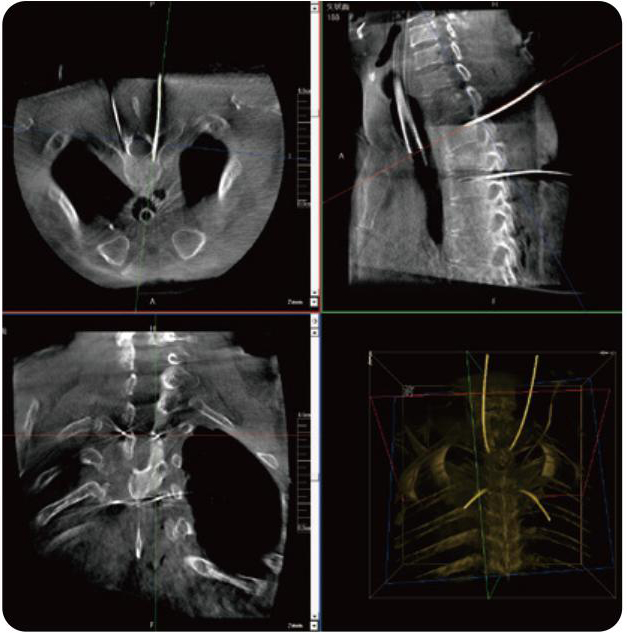

PL300B可應用于多節(jié)段脊柱外科手術,輔助醫(yī)生定位病灶部位,為脊柱外科手術(經(jīng)皮椎體成形術、椎弓根螺釘內(nèi)固定術等術式)提供術前手術流程規(guī)劃、入釘位置、角度可視化引導,模擬仿真入釘輔助。

PL300B搭配普愛醫(yī)療自主研發(fā)生產(chǎn)的平板3D C形臂,借助一體化自適應配準( 軌跡配準)技術,通過追蹤C形臂三維采集軌跡,自動完成圖像坐標建立和系統(tǒng)坐標配準。配準精度更高,操作步驟少,系統(tǒng)運作效率高。